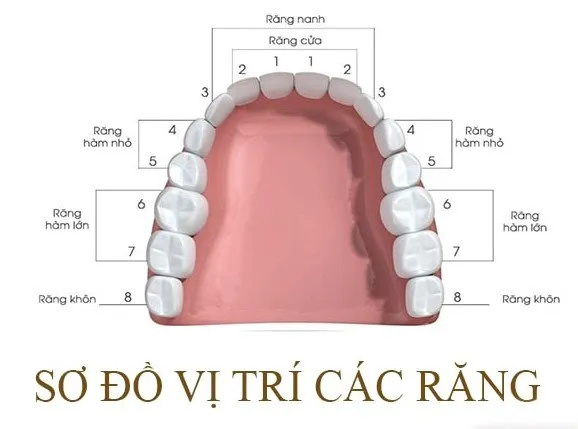

Nguyên nhân khiến răng số 5 cần thay Răng số 5, hay răng cối nhỏ thứ nhất, đóng vai trò quan trọng trong quá trình ăn nhai